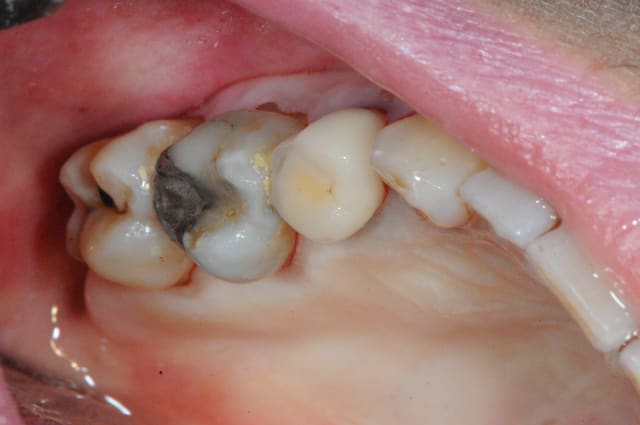

Si cette patiente était vraiment 'motivable' elle n'aurait sans doute pas son gros plombage sur la 6 et il aurait été plus sage de commencer par un inlay sur cette dent qui est un réservoir à bactérie.